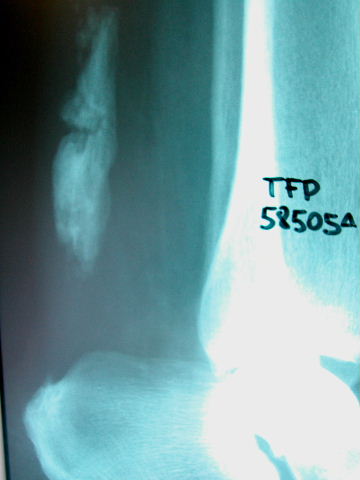

Fractura impactada de húmero .